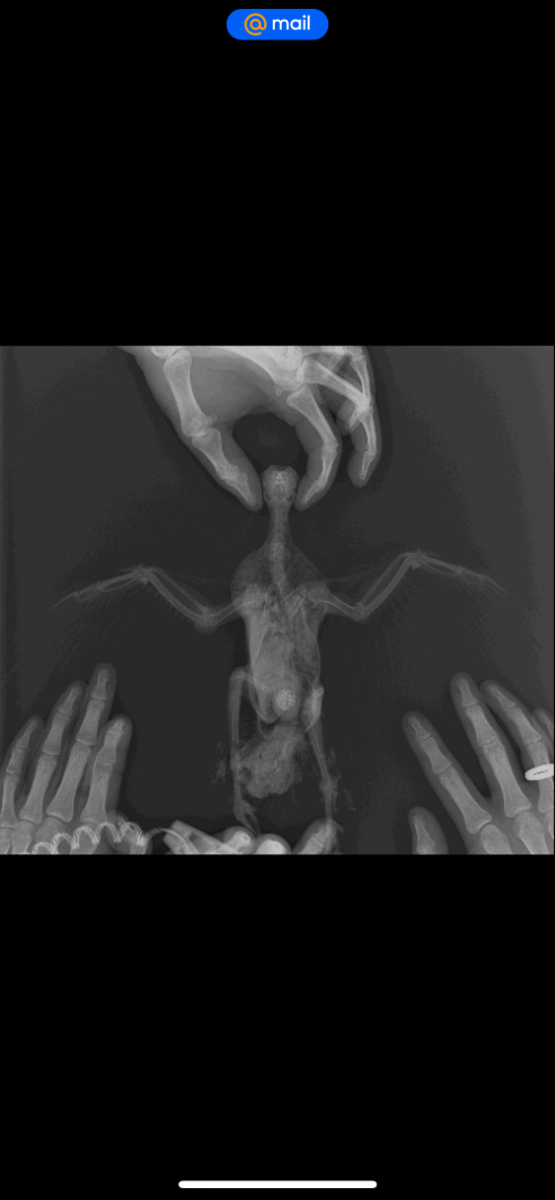

Здравствуйте. Неделю назад нашел голубя. Он просто лежал на спине и не мог встать. Подумал, что его на самокате сбили. Отвез к ветеринару, сделали рентген, который показал, что все норм. Вет.доктор который по птицам должен приехать в клинику через 5 дней. Пока взял его к себе. Он не мог стоять. Его косило и он падал опять на спину. Я его мыл, кормил и поил. Вот уже 4 дня как он стоит, ходит и нормально есть, и пьет. Но его все равно бывает наклоняет на правой бок. На крыле я заметил шишку. Наверное это область локтя. Почитал ваш форму и начал мазать ибупрофеном. Подскажите пожалуйста, что делать. Кто сталкивался с такой ситуацией. Вот симптомы: правое крыло нормально не складывается к спине, немного весит. Голубь бывает заваливается на спину через это же крыло. встать самостоятельно не может. Бывает трясется

рентген нужно чтобы посмотрела @Zosia